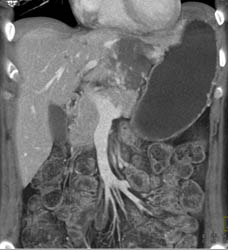

Hemangioma